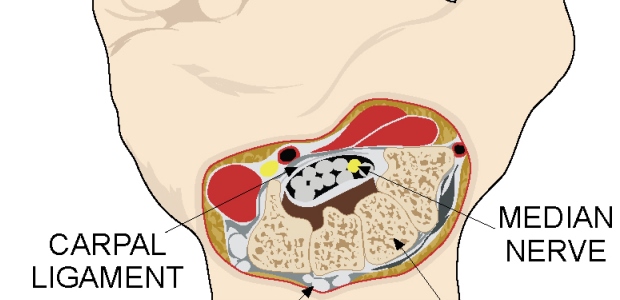

Although CTS is a strong driver of workers' compensation costs, lost wages, lost productivity, and disability, there is still a limited understanding of its frequency and causes in working populations.